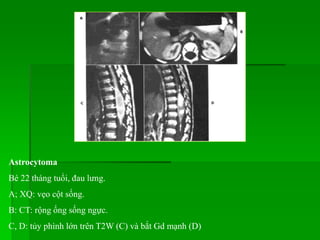

Bé 22 tháng tuổi, đau lưng.

A; XQ: vẹo cột sống.

B: CT: rộng ống sống ngực.

C, D: tủy phình lớn trên T2W (C) và bắt Gd mạnh (D)

Astrocytoma Bé 22 thángtuổi, đau lưng. A; XQ: vẹo cột sống. B: CT: rộng ống sống ngực. C, D: tủy phình lớn trên T2W (C) và bắt Gd mạnh (D)